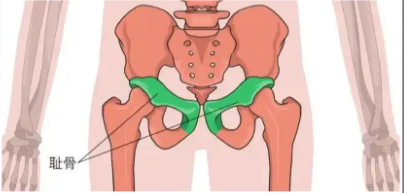

关于骶髂关节,再上一张图来说明一下耻骨的重要性。

图片

女性耻骨位于髋骨前下部,由左右两块骨头组成,通过韧带和软骨连接在一起。耻骨在女性的身体中起着重要的支撑作用,是骨盆的重要组成部分。